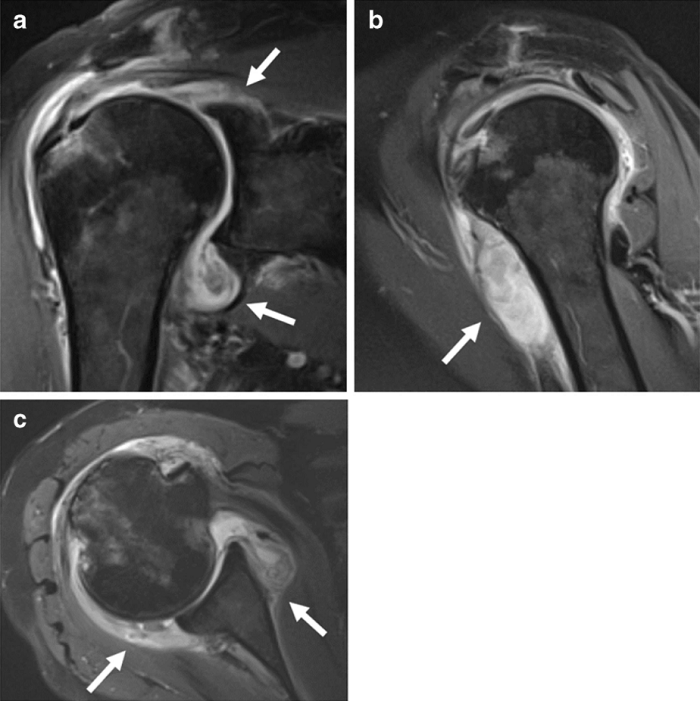

"Podríamos ver edema y cambios inflamatorios de los tejidos (líquido, hinchazón), hematomas (acumulaciones de sangre) o tejido desvitalizado (gangrena) --prosigue--. En algunos pacientes, los nervios están lesionados (brillantes, agrandados) y en otros, el problema es un flujo sanguíneo deficiente (coágulos)".

Por ejemplo, continúa, si un paciente tiene dolor persistente en el hombro que comenzó después de contraer COVID, su proveedor de atención primaria podría solicitar una resonancia magnética / ultrasonido. Si un radiólogo sabe que la COVID puede desencadenar artritis inflamatoria y las imágenes muestran inflamación de las articulaciones, entonces pueden enviar al paciente a un reumatólogo para su evaluación.

"Algunos médicos solicitan imágenes para pacientes con 'dedos de los pies COVID', por ejemplo, pero no había literatura sobre imágenes de las complicaciones del pie y los tejidos blandos de COVID --resalta--. ¿Cómo se encuentra algo si no está seguro de qué buscar? Por eso, en nuestro artículo, discutimos los diversos tipos de anomalías musculoesqueléticas que los radiólogos deben buscar y proporcionar ejemplos de imágenes".